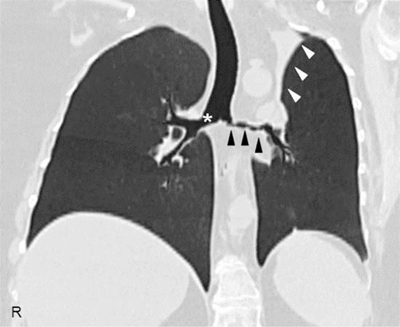

Figure 2

High-resolution computed tomography of the chest, coronal reconstruction, showing a marked wall thickening of the right main bronchus (asterisk), stenosis of the left main bronchus (black arrowheads), and segmental atelectasis in the upper lobe of the left lung (white arrowheads).